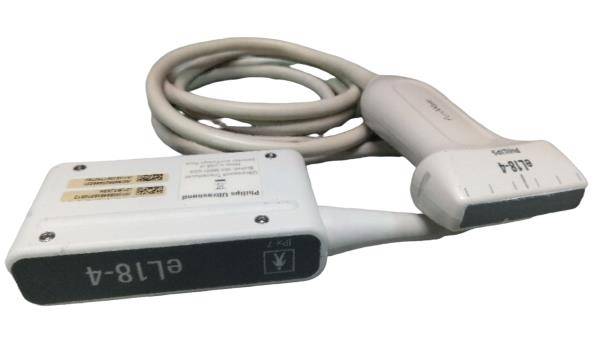

Save $ 359.82

DIAGNOSTIC ULTRASOUND MACHINES FOR SALE

Veterinary Micro convex probe C11 8-5Mhz For Sonosite portable ultrasounds 2008

Sale price$ 1,639.18

Regular price$ 1,999.00